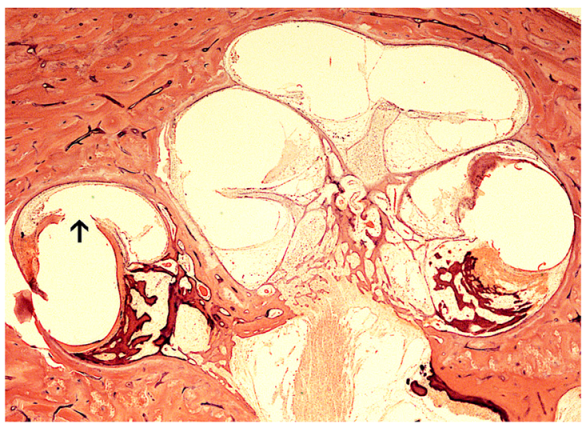

| Ishiyama et al. [19] | 29 HTB histopathology | All 17 bones with cochlear hydrops had implantation by cochleostomy. Fibrosis near the ductus reuniens was associated with cochlear hydrops. Round window technique was associated with minimal fibrosis and was not associated with hydrops. |

| Quesnel et al. [24] | HTB 8 years after Iowa/Nucleus Hybrid S8 with history of delayed loss of residual low frequency hearing at 18 weeks postoperative | Deposition of fibrous tissue and osteoid in the basal turn may cause cochlear mechanical changes. Cochlear hydrops was noted. Organ of Corti and SGN similar to unimplanted contralateral side. |

3.1.1. The Role of Cochlear Hydrops in the Implanted Patient

- Ishiyama, A.; Doherty, J.; Ishiyama, G.; Quesnel, A.; Lopez, I.A.; Linthicum, F.H. Post hybrid cochlear implant hearing loss and endolymphatic hydrops. Otol. Neurotol. 2016, 37, 1516–1521. [Google Scholar] [CrossRef]